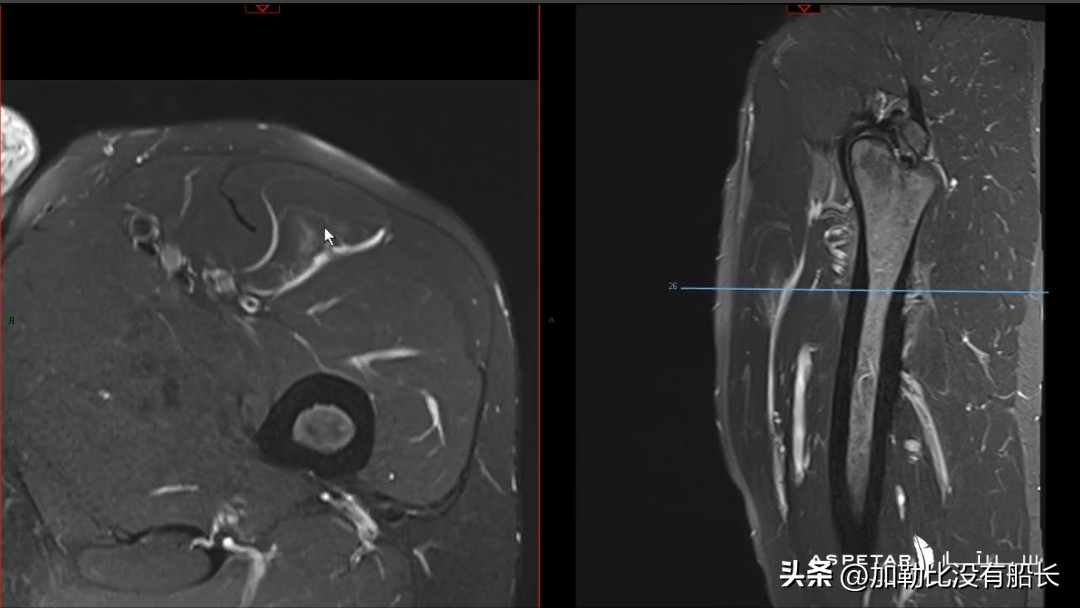

球员经纪人立马晒出检查照片予以回击,“本泽马离开一周后就恢复了跑步和训练,再4天后就在皇马的友谊赛中踢了30分钟,我把这个放在这,在此之前,我问过三位专家,他们都确认,本泽马至少从世界杯1/8淘汰赛开始可以替补出场!为什么你们让他这么快就离开球队!但继续撒谎吧,真相就要揭晓。”最终谁是谁非,时间还是会给出一个最公正的答案。